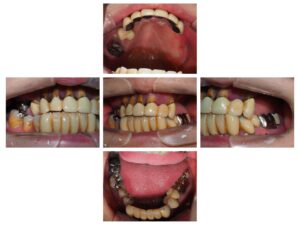

前歯が6本ぐらぐらして、総入れ歯になるのが嫌なのでなんとかしてほしいということで来院されました。

パントモ、CT、スキャンを行い、仮歯の印象をしました。(増歯)